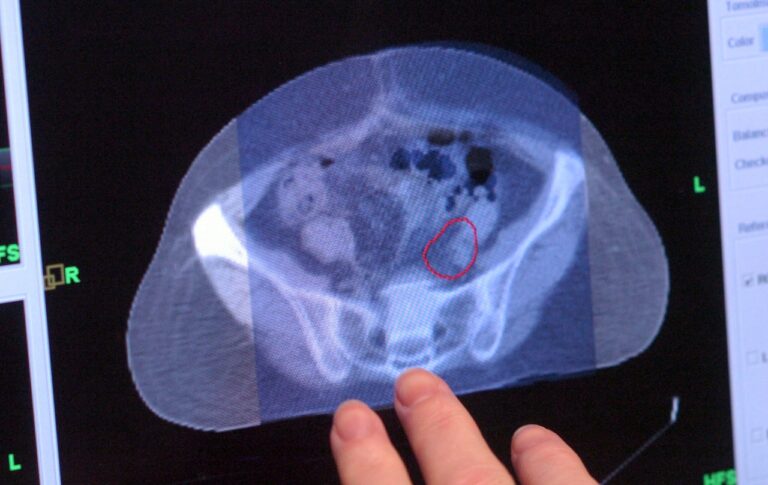

Colorectal cancer is increasingly affecting younger populations. This alarming trend highlights the importance of awareness and early detection. Experts emphasize...

Rising Threat of Colorectal Cancer among Young AdultsColorectal cancer emerged as the leading cause of cancer death among individuals under...